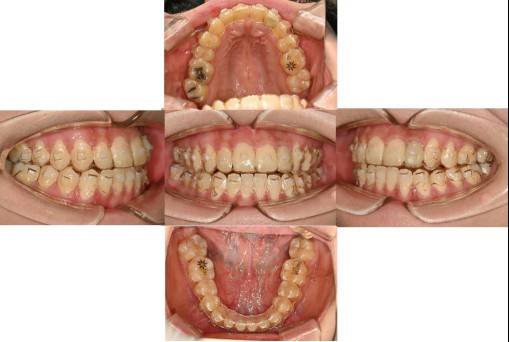

Does this look like ordinary orthodontic treatment to you?

Dentists around the world must recognize that treating patients based on the conventional habitual jaw position can significantly impact their lives.

Yesterday, a person from Canada came in; this individual had undergone extraction orthodontics and whom I had consulted with online three years ago.